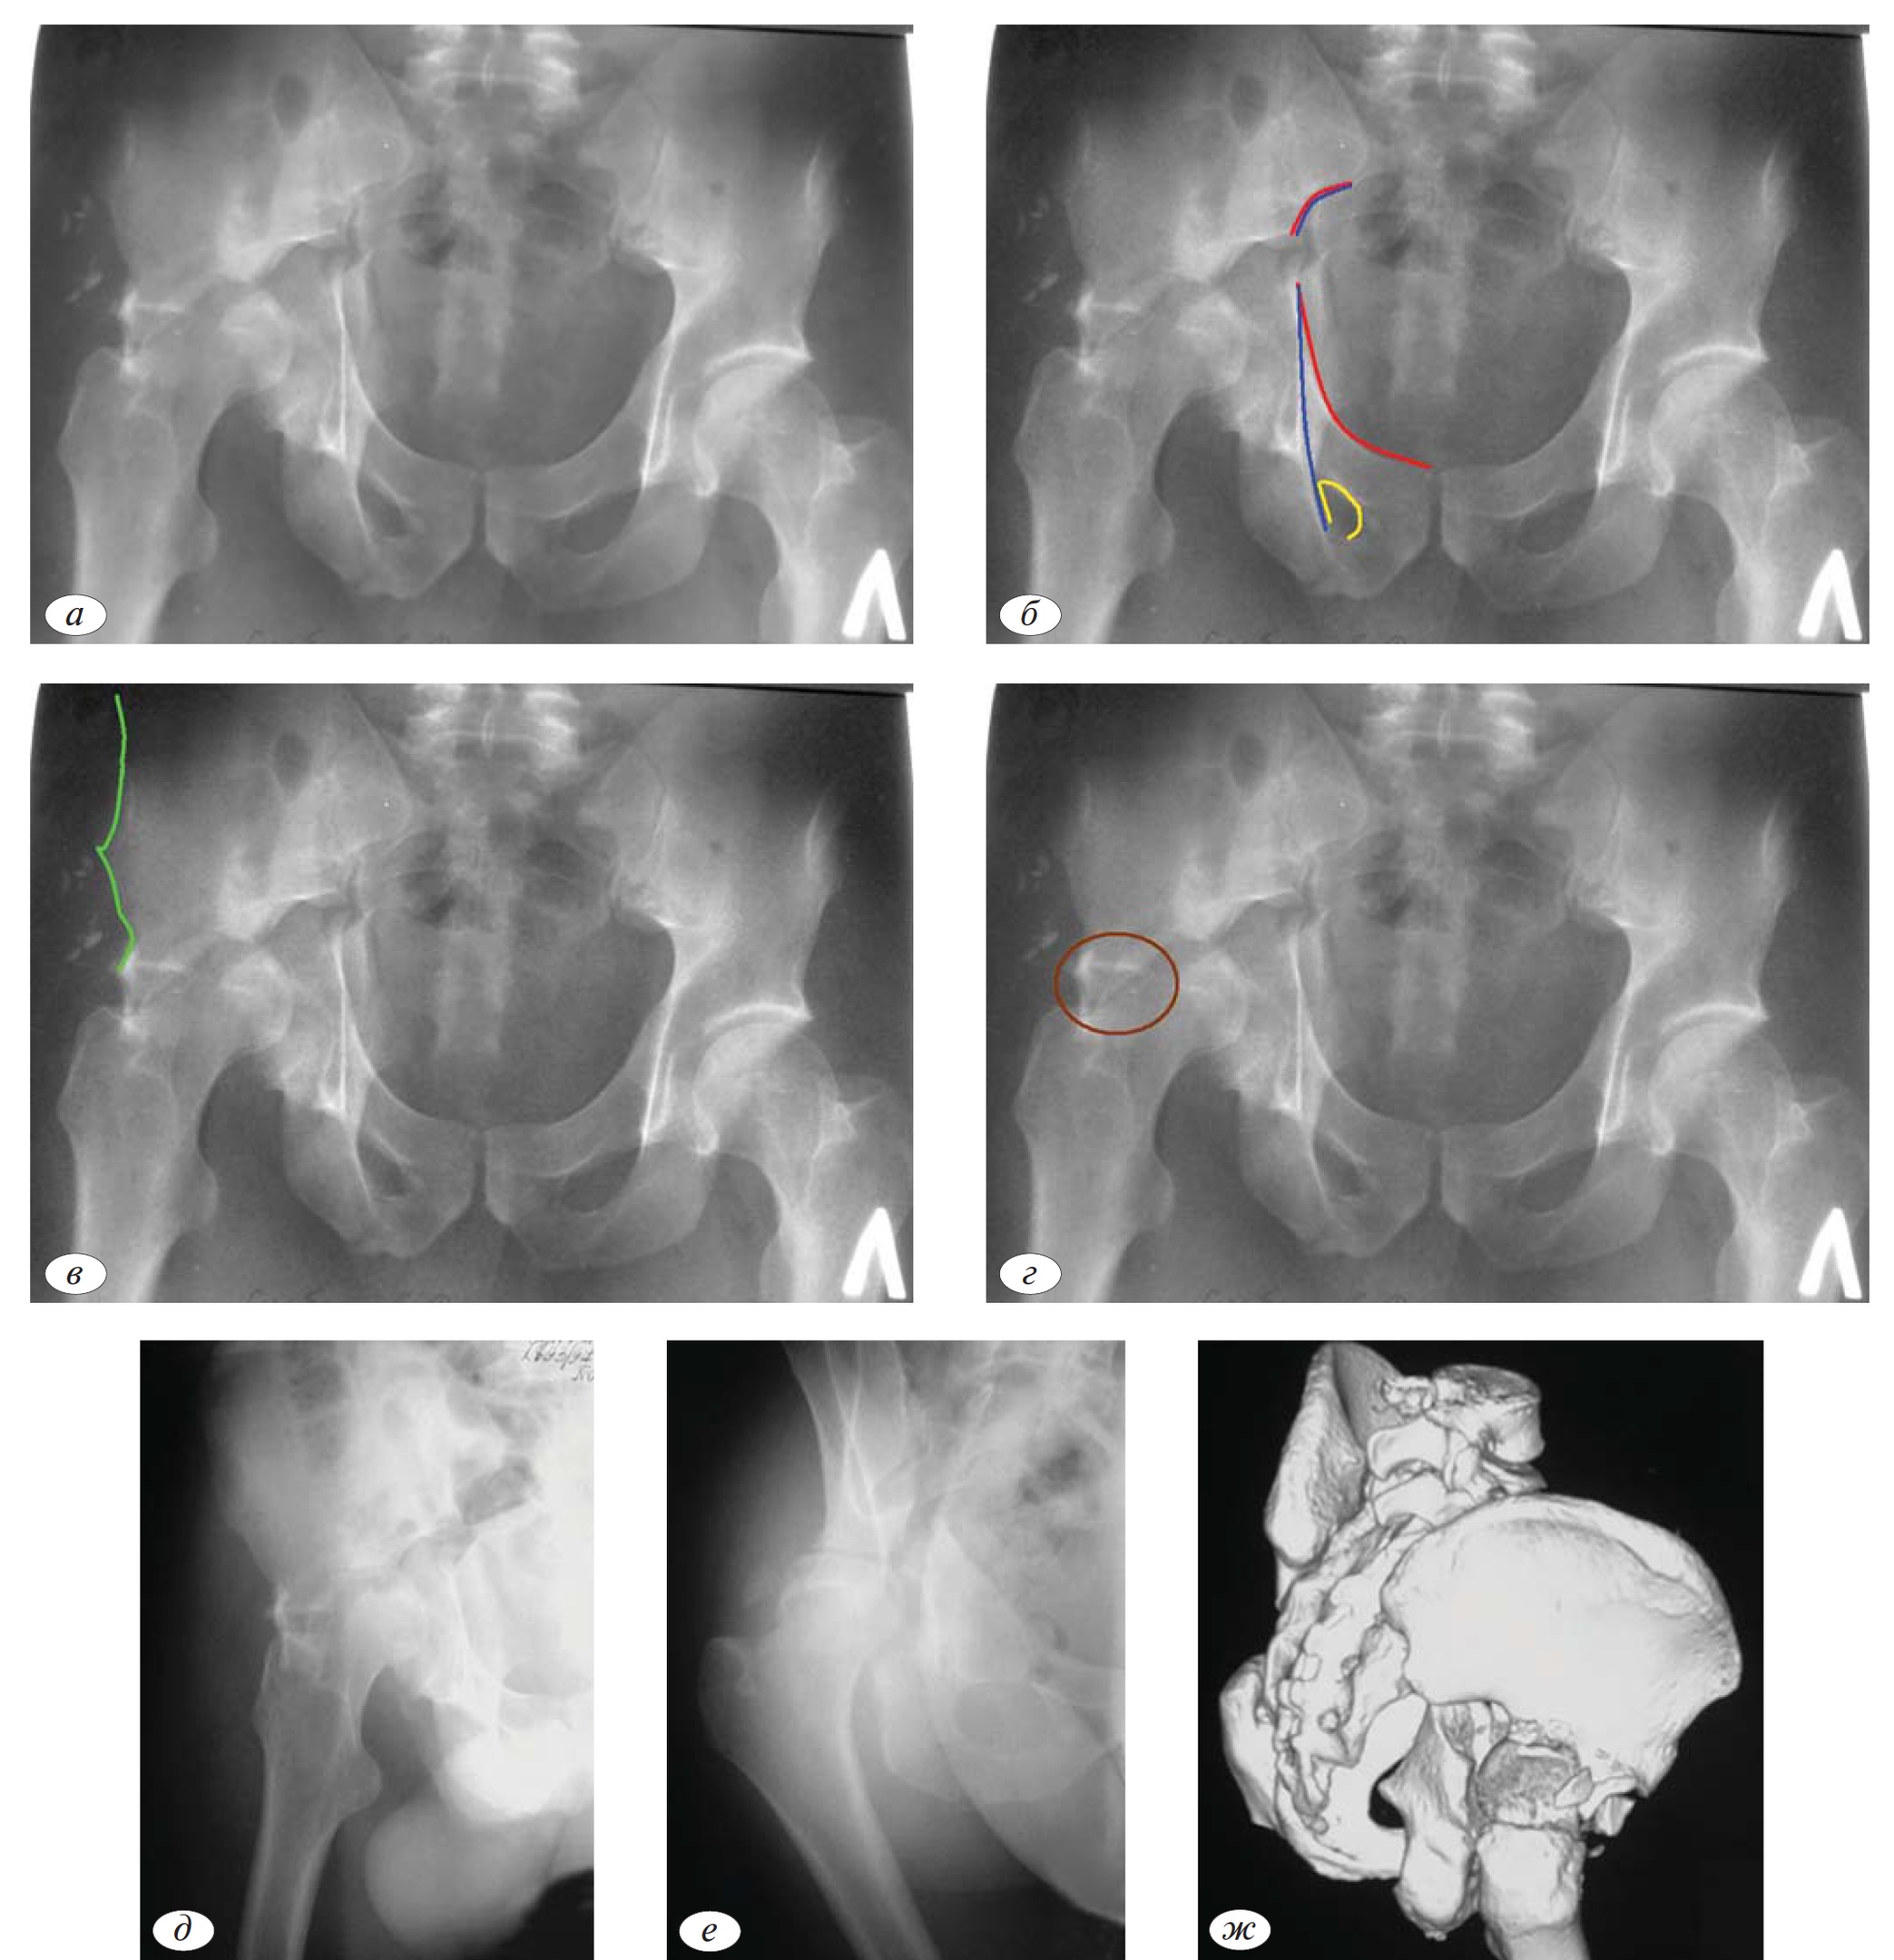

У пожилых пациентов нередко возникает импакция верхнемедиальных отделов сурсила (крыши вертлужной впадины). Локализация импакции в этих отделах вертлужной впадины обусловлена типичным механизмом травмы для этих пациентов — падение с высоты собственного роста, когда головка бедренной кости при соударении «проминает» субхондральную порозную губчатую кость крыши вертлужной впадины. Рентгенологически это повреждение описано, как крыло морской чайки (Gull-sign) (рис. 5) [5].

Рис. 5. Импакция верхнее-медиальных отделов сурсила (Gull-sign).

Рис. 6.а—г. Наличие теней костной плотности в проекции суставной щели (внутрисуставные осколки); в, г — верификация наличия внутрисуставных осколков по данным КТ.

Сложность рентгенологической анатомии тазобедренного сустава значительно затрудняет выявление внутрисуставных отломков. Заподозрить наличие внутрисуставных осколков возможно при наличии теней костной плотности в проекции суставной щели как минимум в 2 проекциях (рис. 6, а—г).

Однако окончательная диагностика этого сопутствующего локального компонента повреждения возможна с помощью КТ (рис. 6д, е).

Переломы головки чаще встречаются при переломах вертлужной впадины с локализацией очага в задних отделах (задняя колонна, задняя стенка). Перелом головки довольно часто носит импрессионный характер и проявляется в виде участка вдавления верхнего полюса головки (рис. 7, а, б). Наиболее часто повреждения головки бедренной кости наблюдаются у пациентов старше 40 лет, что обусловлено снижением качества костной ткани.

В некоторых случаях импрессионных переломов головки рентгенография не является достаточно убедительной для верификации. Окончательное определение повреждения головки бедренной кости проводим по данным КТ (рис. 8, а, б). Сочетание перелома вертлужной впадины и нагружаемой части головки бедренной кости является крайне неблагоприятным прогностическим признаком.

Рис. 7. Импрессионный перелом головки в сочетании с переломом задней колонны (а, б).

Рис. 8. Импрессионный перелом головки бедренной кости по данным КТ при отсутствии признаков повреждения головки по данным рентгенографии (а, б).